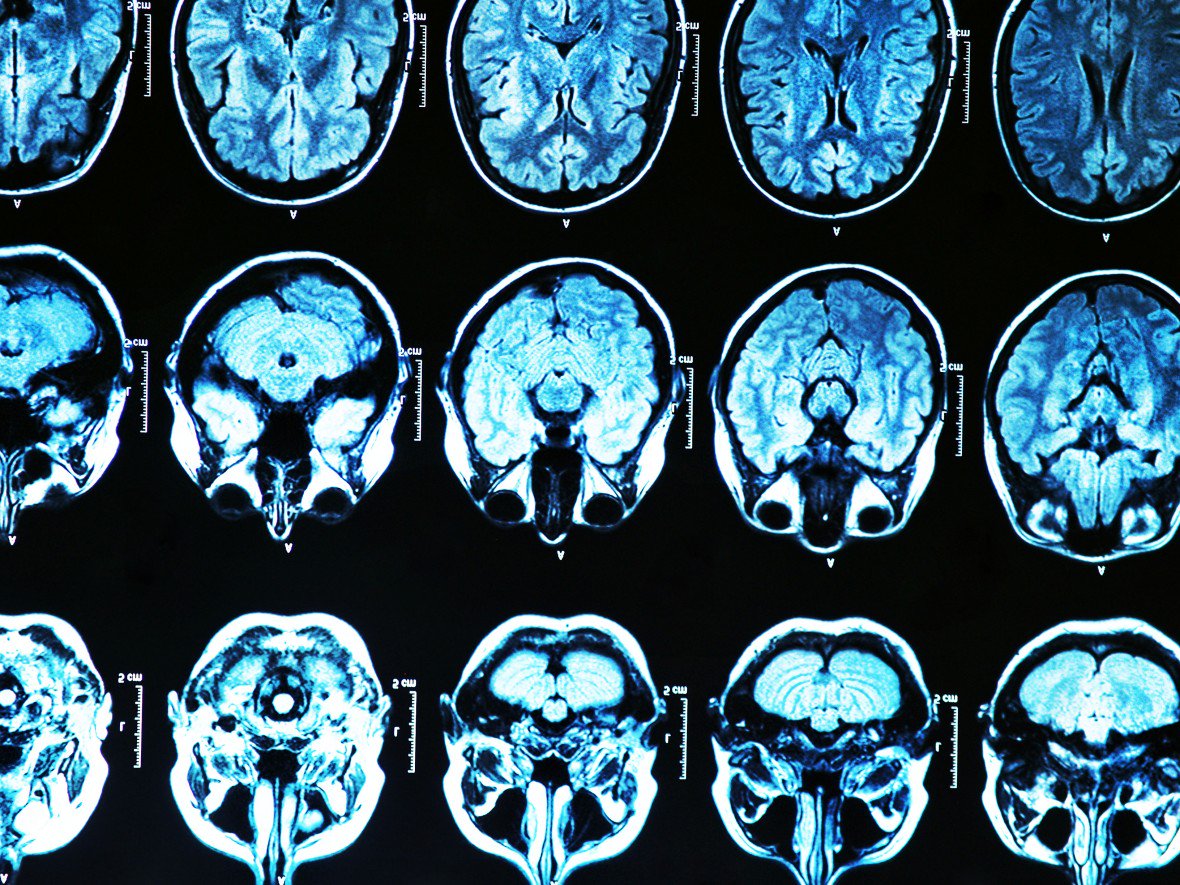

روش ژن‌تراپی جدید برای مقابله با آلزایمر

حمید نیک روش - ICTPRESS - پزشکان نیویورک سیتی به زودی تست یک روش ژن تراپی جدید را برای مقابله با بیماری آلزایمر آغاز می‌کنند.